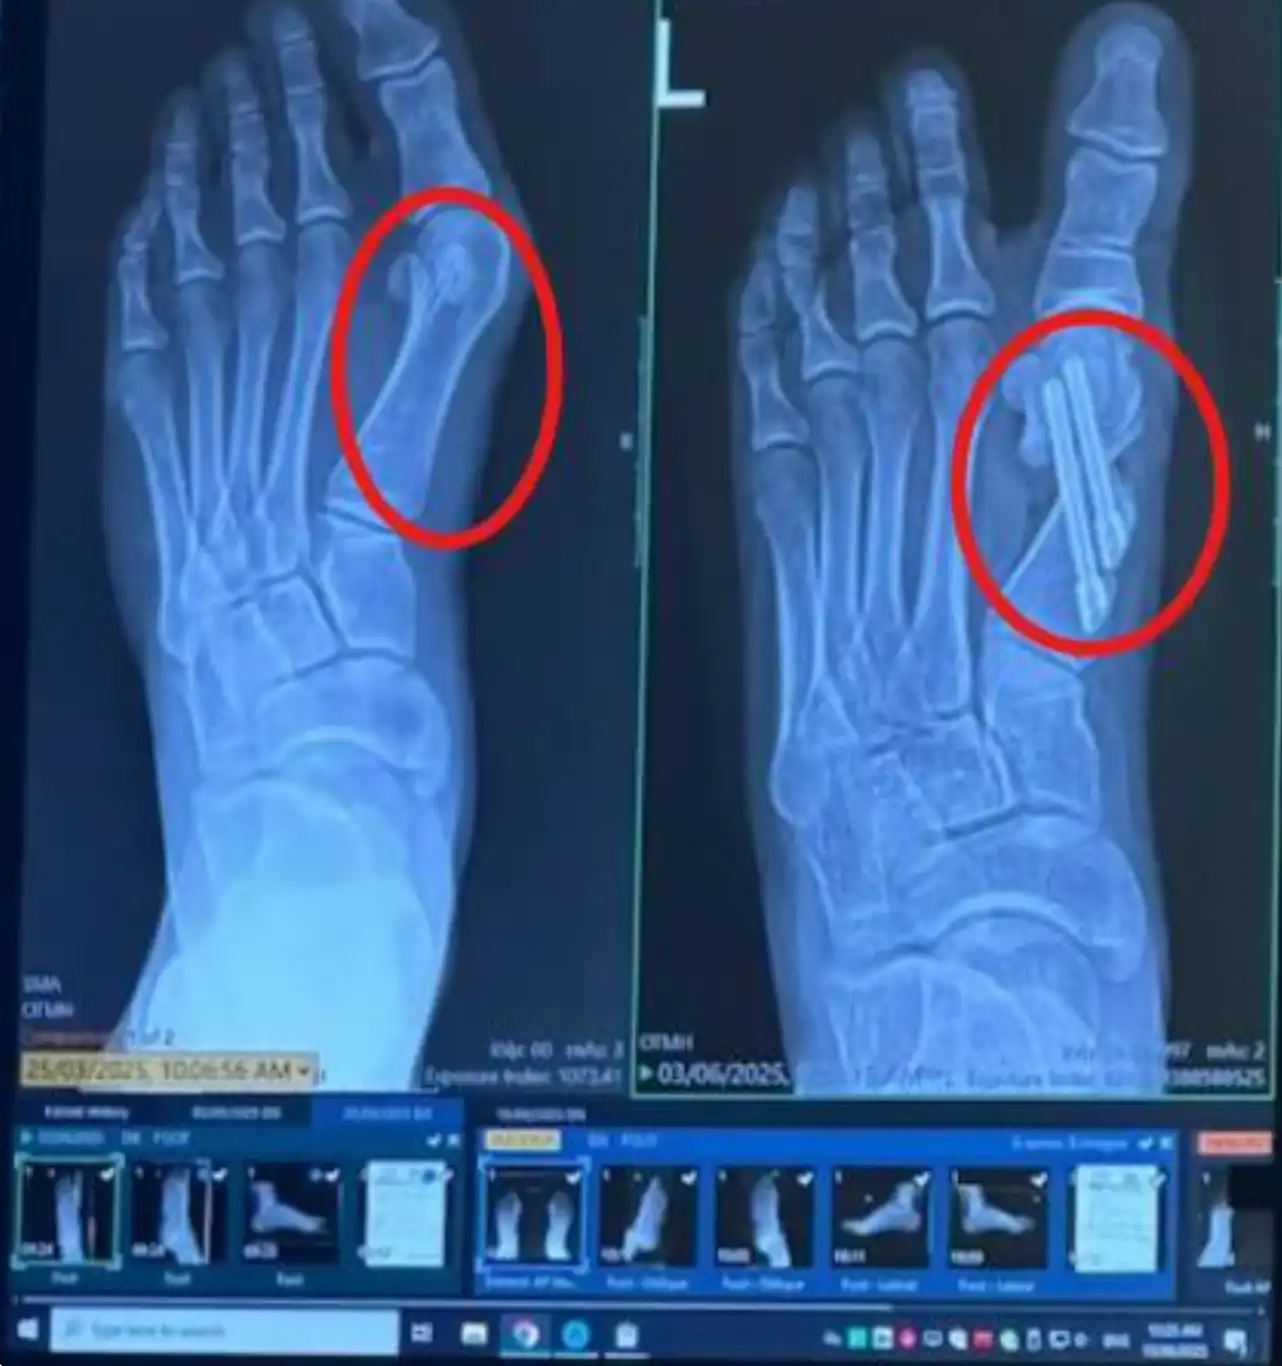

ذلك البروز المؤلم ليس مجرد "عظمة زائدة" تحتاج لعملية جراحية لإزالتها.

الحقيقة هي أن إصبع قدمك الكبير ينحني بعيداً عن مساره الطبيعي.

لماذا تفشل عمليات "الوكعة" الجراحية؟

ما يقارب 30-50% من العمليات الجراحية إما تفشل أو تؤدي إلى تيبس طويل الأمد، ظهور ندبات، أو حتى عودة الألم من جديد.

فترة التعافي؟ توقع قضاء 6-12 أسبوعاً دون القدرة على المشي، واستخدام العكازات، مع خطر عودة المشكلة إذا لم تلتزم بارتداء الأحذية الطبية مدى الحياة.

هذه الجراحات لا تعالج "جذر المشكلة". فهي تعتمد ببساطة على القص واستخدام البراغي لإعادة تثبيت مفاصل أصابعك.